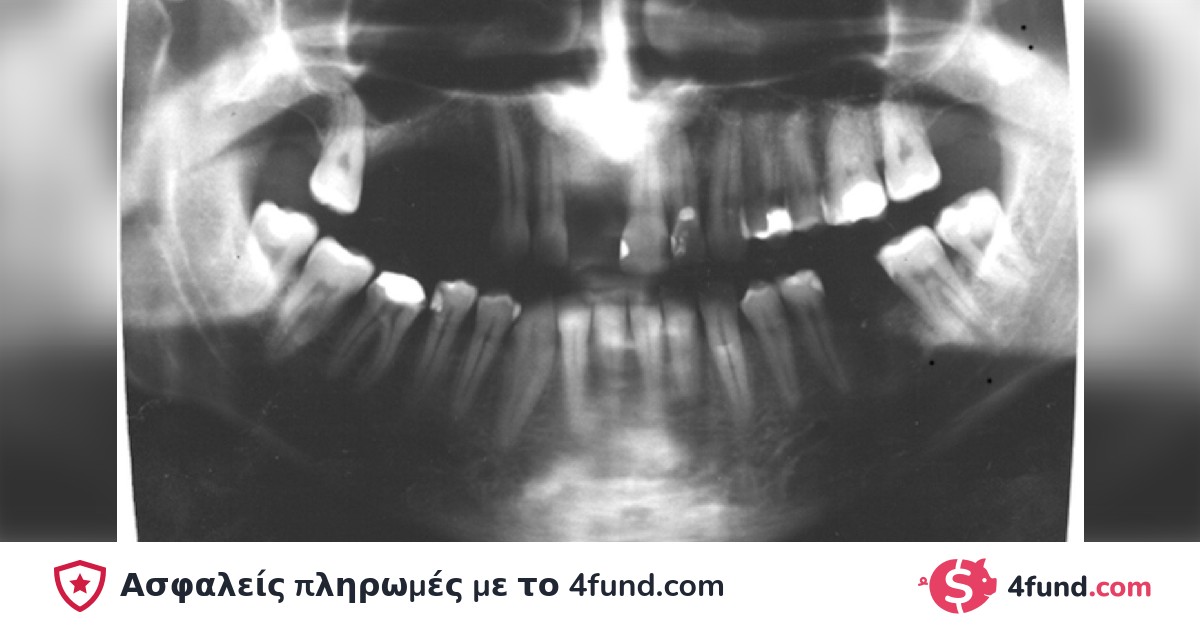

In 1992, a doctor extracted my tooth 2.4 and filed teeth 2.5 and 2.6 to replace the extracted tooth with a prosthesis, but part of the root of the tooth breaks and remains on the arch because the doctor did not check the extracted tooth.

10 years later, the rest of my remaining tooth destroyed an arch!